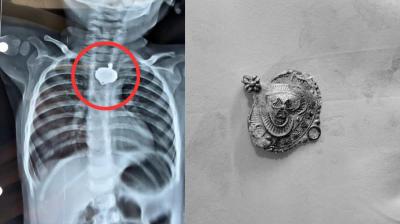

बड़वानी में 9 माह के बच्चे की आहार नली में फंसा मंगलसूत्र, डेढ़ महीने बाद एक्स-रे से खुलासा

24 Nov, 2025 08:30 AM IST | PRADESHJANWARTA.IN

बड़वानी: रविवार को जिला अस्पताल में एक बेहद संवेदनशील और हैरान करने वाला मामला सामने आया. जब 9 माह के एक बच्चे के गले में मंगलसूत्र फंसा हुआ देखा गया. घटना...